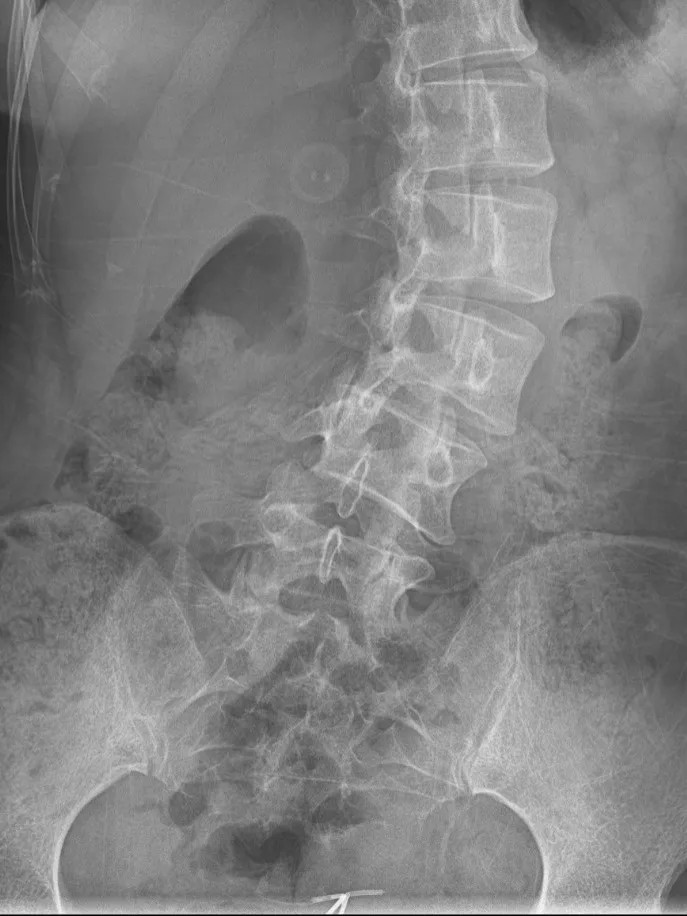

DR影像顯示:

1、脊柱下胸椎及腰椎“S”形側(cè)彎、旋轉(zhuǎn)。

2、頸椎曲度改變。

經(jīng)過站立位全脊柱X線檢查,文女士(化名)的脊柱側(cè)彎進(jìn)一步明確,而且不僅有側(cè)彎(側(cè)彎49.46度),還有腰椎間盤突出,是由發(fā)育期不良坐姿導(dǎo)致的。